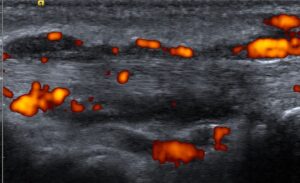

Tenosinovita, intens activa (semnal Doppler intens)